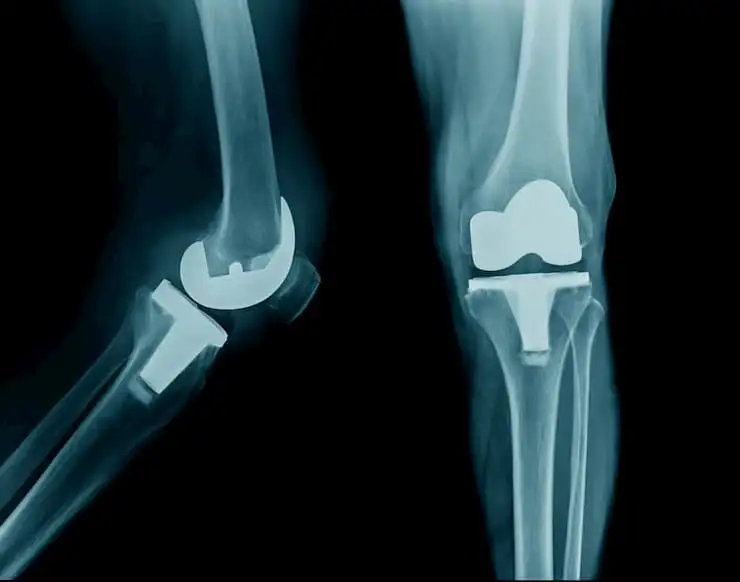

Эффективность сочетанного применения дулоксетина для приема внутрь и внутрисуставных инъекций при остеоартрозе коленного сустава

Было проведено проспективное рандомизированное открытое исследование для определения полезности комбинации дулоксетина и инъекций гиалуроновой кислоты (ГК) и кортикостероидов (КС) при остеоартрозе коленного сустава.

У пациентов с остеоартрозом коленного сустава прием дулоксетина наряду с внутрисуставным введением кортикостероида в сочетании с гиалуроновой кислотой эффективно облегчает боль и улучшает функцию коленного сустава.

Сочетанное применение дулоксетина и внутрисуставных инъекций (ГК + КС) обеспечивало существенное облегчение боли и улучшение функции коленного сустава по сравнению с внутрисуставными инъекциями в качестве монотерапии.